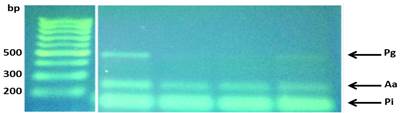

Se realizaron PCR con cada par de oligonucleótidos utilizando los genomas extraídos de la cepa silvestre. Los cebadores utilizados para la detección de las especies bacterianas A. actinomycetemcomitans, P. gingivalis, P. intermedia, T. forsythia y F. nucleatum fueron los que se muestran en la Tabla 1. Las condiciones de las PCR multiplex para la detección de estos microorganismos se muestran en las Tablas 2 y 3.

La visualización de los resultados de las amplificaciones (bandas) se realizaron en geles de agarosa al 1.2%, buffer TBE (Tris-borato-EDTA) 0.5x, 5µl de GoodView, 2µl de cyan/orangeloading buffer; 2-5 µl del producto del PCR durante 2h a 80V; y fotografiados con una cámara digital colocada encima de un transiluminador con luz ultravioleta (UV) (Figs. 4 y 5).